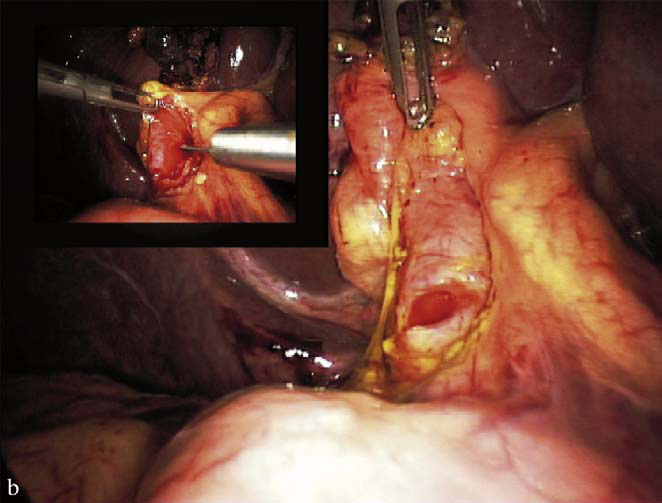

4.4. Phẫu thuật nội soi lấy sỏi ống mật chủ có hoặc không kèm theo dẫn lưu Kehr

Hình 10. Phẫu thuật nội soi lấy sỏi ống mật chủ [5]

Về chỉ định:

- Sỏi đường mật chính đơn thuần.

- Sỏi đường mật chính kết hợp sỏi túi mật.

Ưu điểm:

- Hậu phẫu nhẹ nhàng, bệnh nhân ít đau sau mổ.

- Thời gian nằm viện ngắn.

- Là một phẫu thuật ít gây sang chấn.

- Thẩm mỹ cao.

- Giảm nguy cơ dính ruột sau mổ về sau.